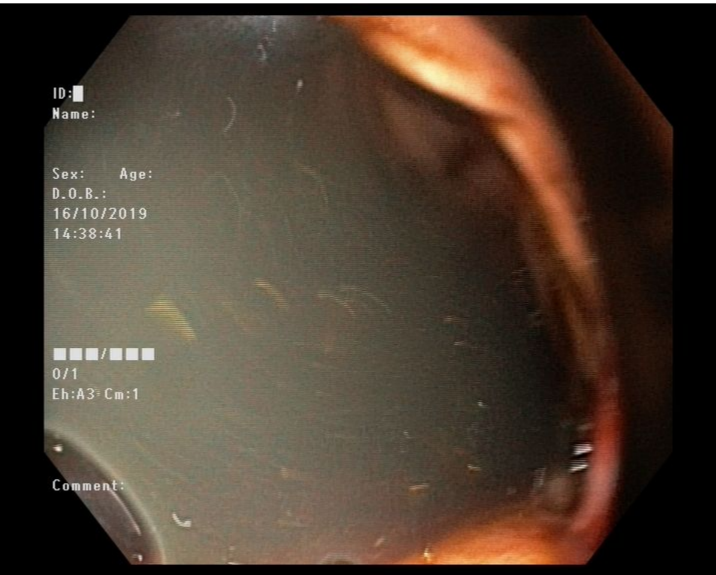

GI ENDOSCOPY-Training

KGC’s GI Endoscopy – Hands-on Training Series offers comprehensive training in advanced endoscopic techniques, practical skills, live demonstrations, expert-led sessions, interactive workshops, and personalized feedback to enhance clinical proficiency.

Gi Endoscopy

Master GI Endoscopy for enhanced practice. Learn diagnostic and interventional techniques & make Flexible GI Endoscopy an integral part of your practice.